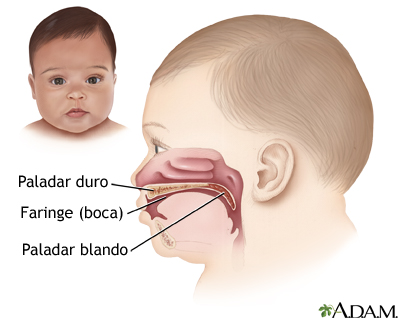

La cavidad oral o bucal, puerta de entrada al tubo digestivo, es una cavidad de

tipo virtual ocupada casi en su totalidad por el órgano lingual en estado de

reposo.

Está limitada antero-lateralmente por los labios y mejillas o carrillos,

dorsalmente por la bóveda palatina, velo del paladar y faringe, ventralmente por

la lengua y el piso de la boca y en su parte posterior por la entrada de la

orofaringe o istmo de las fauces.

La cavidad oral se encuentra dividida en dos zonas cuando los maxilares se

encuentran en oclusión: una comprendida por dentro de las arcadas dentarias,

denominada boca propiamente tal y otra ubicada entre los labios y las mejillas,

y las arcadas dentarias, denominada vestíbulo.

El vestíbulo y la cavidad bucal se encuentran comunicadas entre sí a través de

los espacios interdentarios y el espacio retromolar (zona ubicada entre la cara

distal de los últimos molares y la rama del maxilar inferior).

Los órganos que conforman el sistema bucal son:

v Los labios.

v Las mejillas.

v La lengua.

v El paladar duro y blando.

v Los dientes.

v El periodoncio de protección.

v Las glándulas salivales.